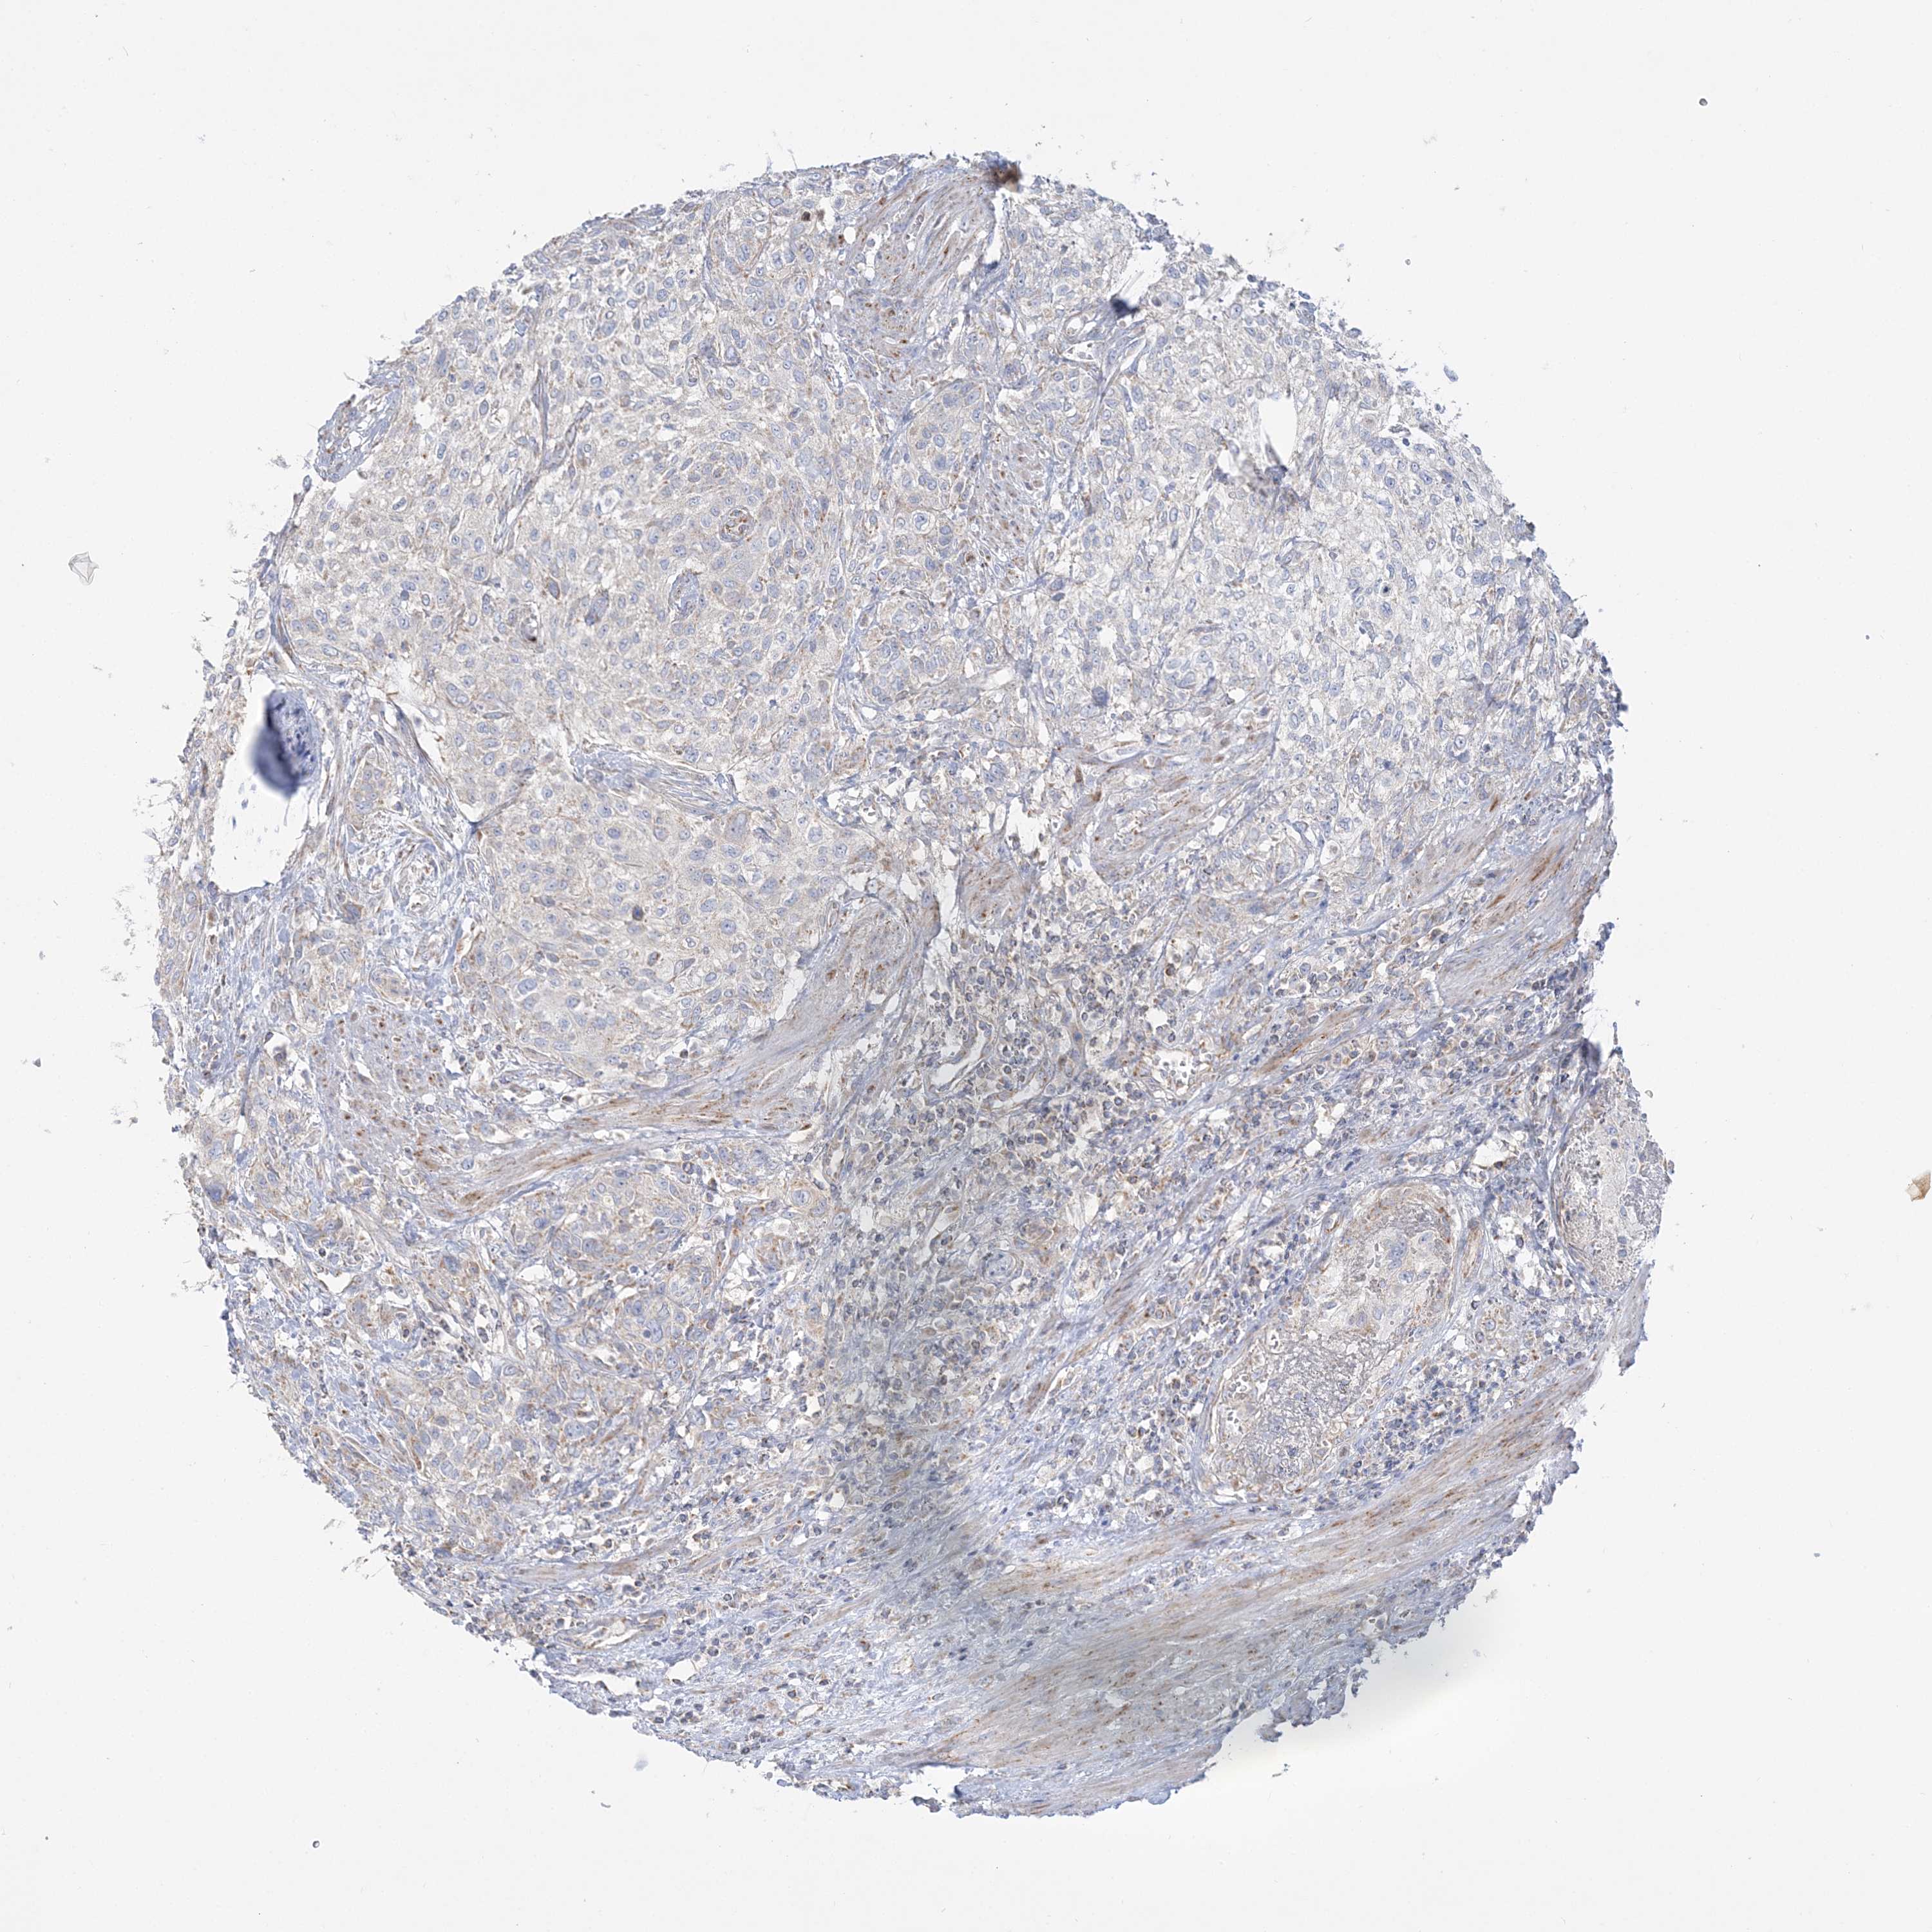

UROTHELIAL CANCER - Protein expressioni

A mouse-over function shows sample information and annotation data. Click on an image to view it in a full screen mode. Samples can be filtered based on level of antibody staining by selecting one or several of the following categories: high, medium, low and not detected. The assay and annotation is described here.

Note that samples used for immunohistochemistry by the Human Protein Atlas do not correspond to samples in the TCGA dataset.

Antibody stainingi

Antibody staining in the annotated cell types in the current human tissue is reported as not detected, low, medium, or high, based on conventional immunohistochemistry profiling in selected tissues. This score is based on the combination of the staining intensity and fraction of stained cells.

Each image is clickable and will lead to virtual microscopy that enables deeper exploration of all samples and also displays staining intensity scores, fraction scores and subcellular localization as well as patient and tissue information for each sample.

Antibody HPA036930

Staining

High

Medium

Low

Not detected

Intensity

Strong

Moderate

Weak

Negative

Quantity

>75%

75%-25%

<25%

None

Location

Nuclear

Cytoplasmic/membranous

Cytoplasmic/membranous,nuclear

Urothelial carcinoma, High grade

Urothelial carcinoma, Low grade